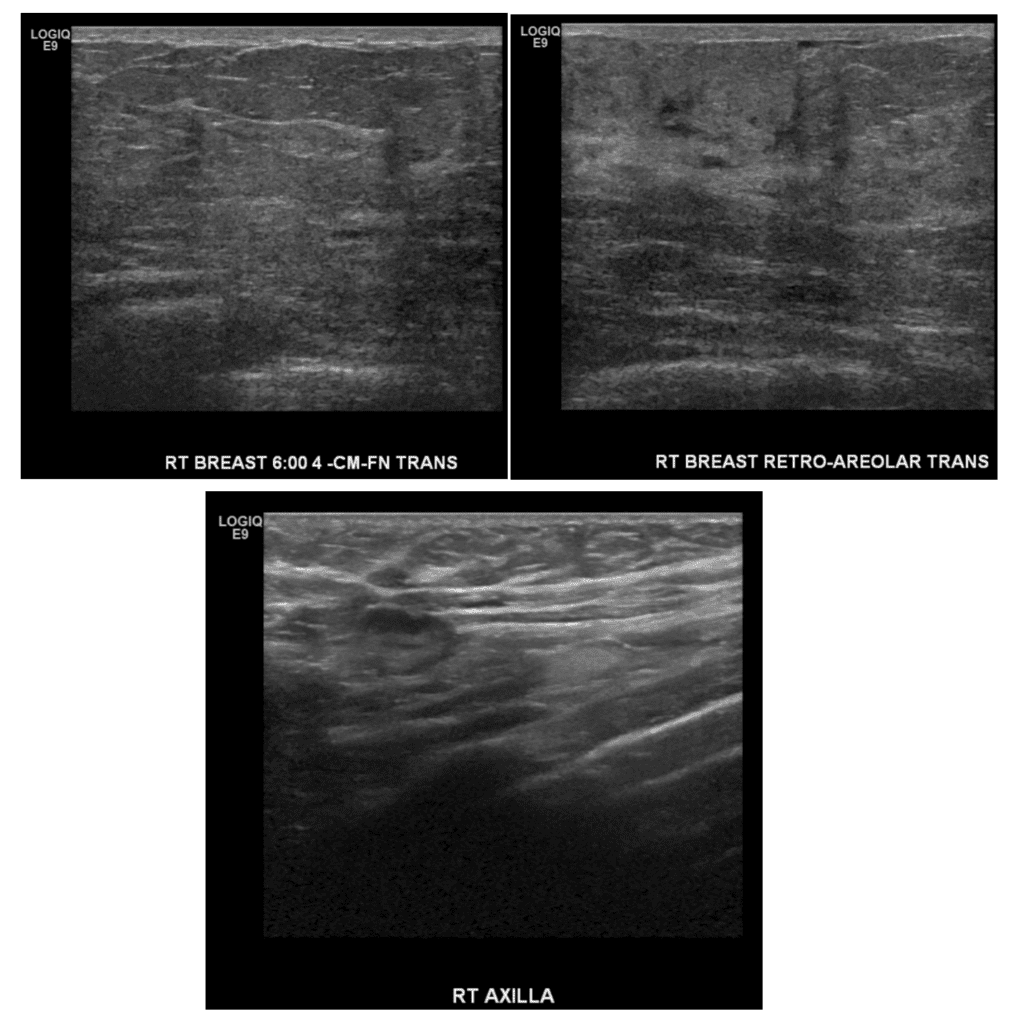

Ultrasound screening during lactation in BRCA I patient